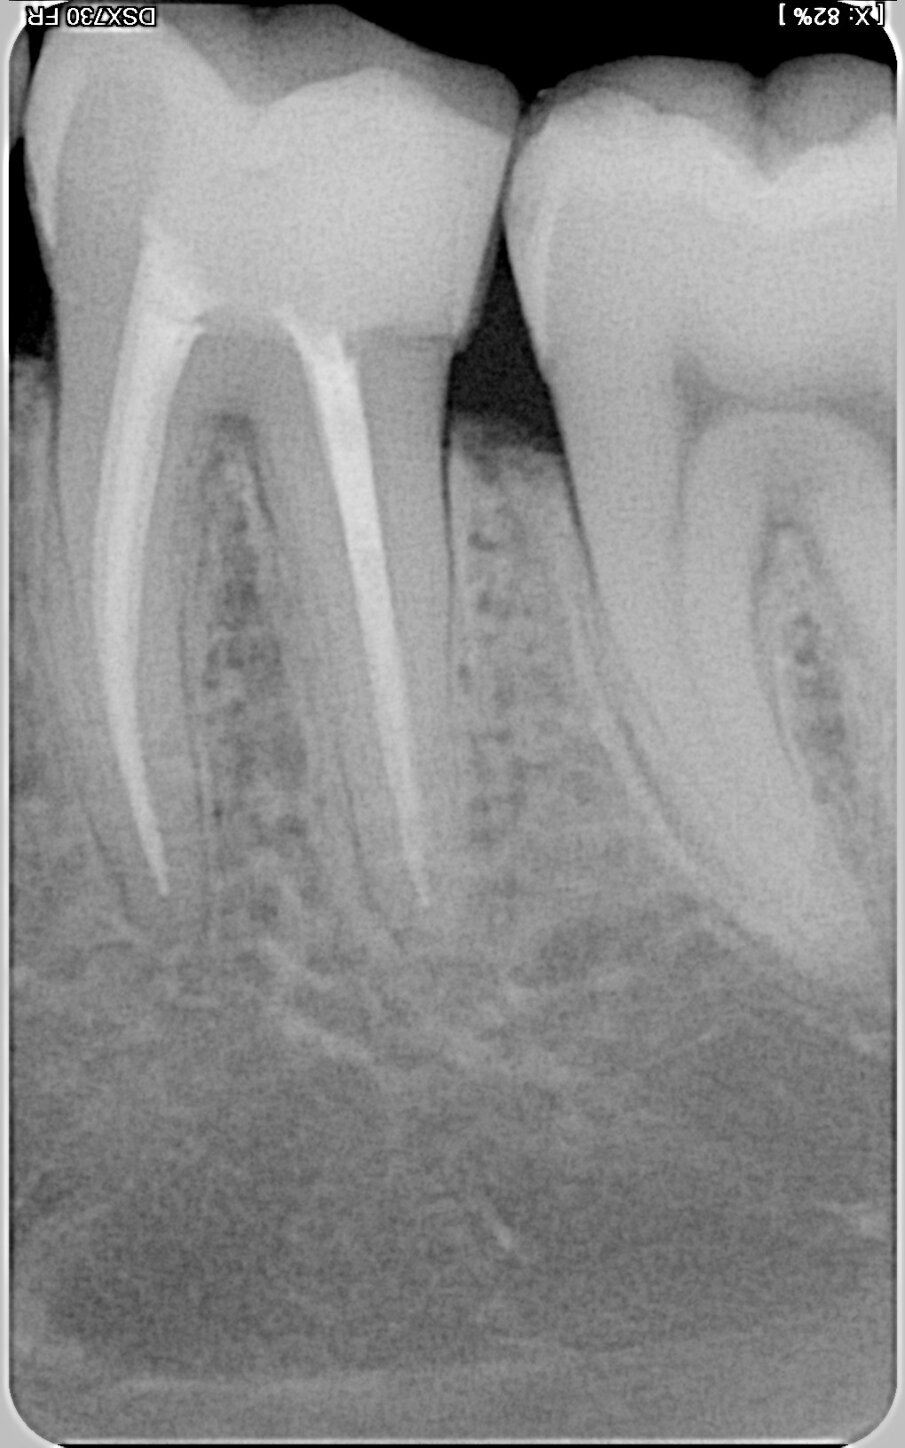

A revision treatment by Dr Silviu Bondari from Beuzeville in France also demonstrates that retreatment can be performed quickly and easily with the new endodontic motor. In a 30-year-old patient, removal of the insufficient gutta- percha filling also proved necessary owing to periapical periodontitis in tooth #36 (Fig. 4). At a speed of 1,000 rpm with continuous rotation, a delicate MicroMega Remover file was inserted to over two-thirds of the distal root canal length. The remainder of the root was then treated with a HyFlex EDM OneFile in the contra-angle handpiece at 500 rpm. HyFlex EDM files of size 20/.05 were used in the mesial root canals. The speed was also set at 500 rpm. The HyFlex EDM OneFile was then used in the mesial canals for final shaping of the root canal. A 40/.04 EDM file was used in the distal root canal. The result on the radiograph promised a more durable obturation than the initial treatment five years earlier (Figs. 5 & 6).